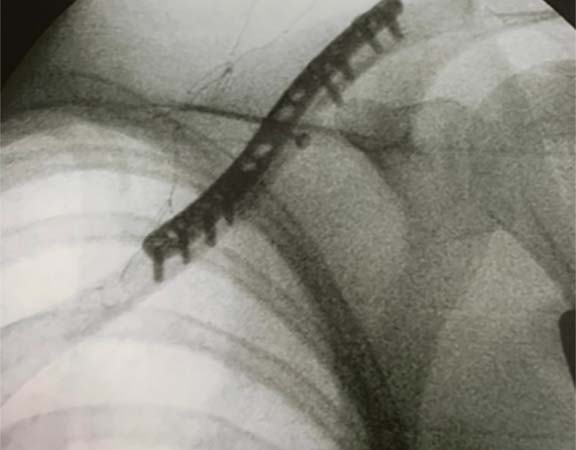

FRATURA DA CLAVICULAR

A clavícula é o osso responsável em ligar o esqueleto axial ao membro superior. A fratura deste osso é comum, e acomete principalmente homens jovens com idade abaixo de 20 anos, após uma queda sobre o ombro. A maioria (80-85%) das fraturas da clavícula ocorrem no terço médio. Geralmente apresenta inchaço, com arroxeado local de pele e geralmente com a movimentação se ouve pequenos estalos Essas fraturas, quando com pouco desvio, podem ser tratadas conservadoramente com imobilização. Em casos de cirurgia existem 2 opções principais: colocação de placa e parafusos ou uma haste intramedular.